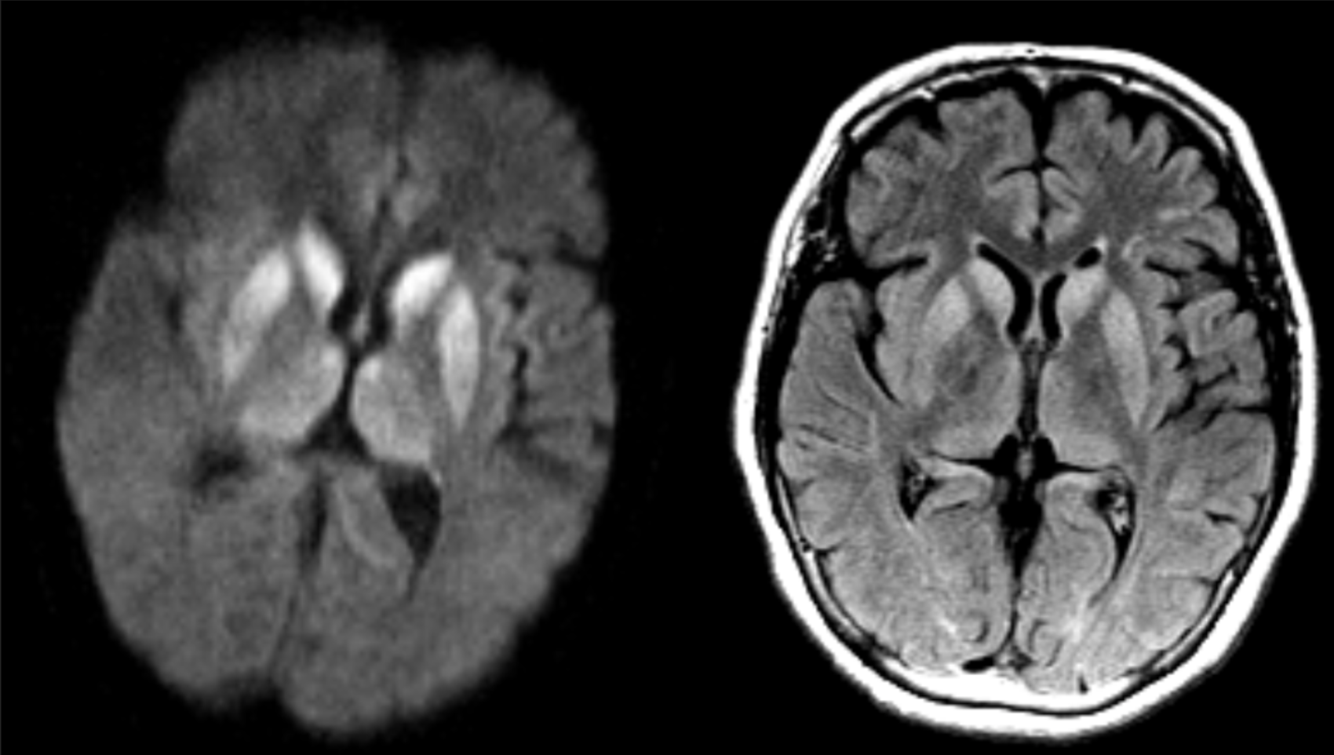

A 65 year-old man presented with the rapid-onset rapid progression of dementia and myoclonus.

Creutzfeldt-Jakob Disease (CJD) with cortical ribboning